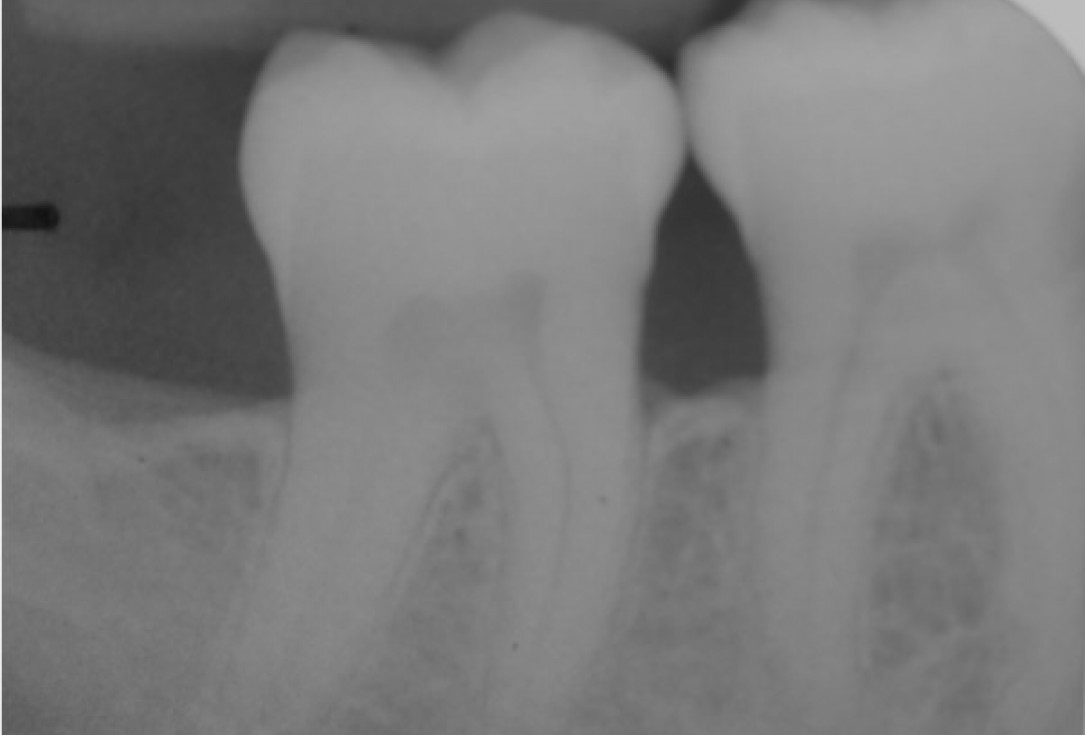

04/22 - Pre-operative radiograph. Deep intrabony defect visible mesially to tooth 45.

Deep intrabony defects treated using Straumann® Emdogain® - Dr. M. Stefanini